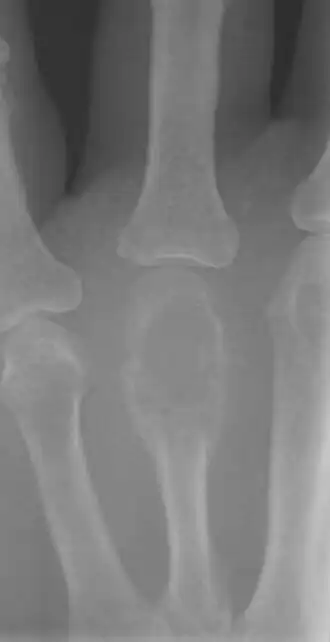

• Encondroma: geralmente aparece nos ossos da mão e do pé. Muitas vezes não tem sintomas. É o tipo mais comum de tumor na mão.

Frequentemente são um achado incidental em um raio-X ou tomografia computadorizada feito para outro problema. Uma biópsia permite diferenciar entre os tipos de tumores ósseos.